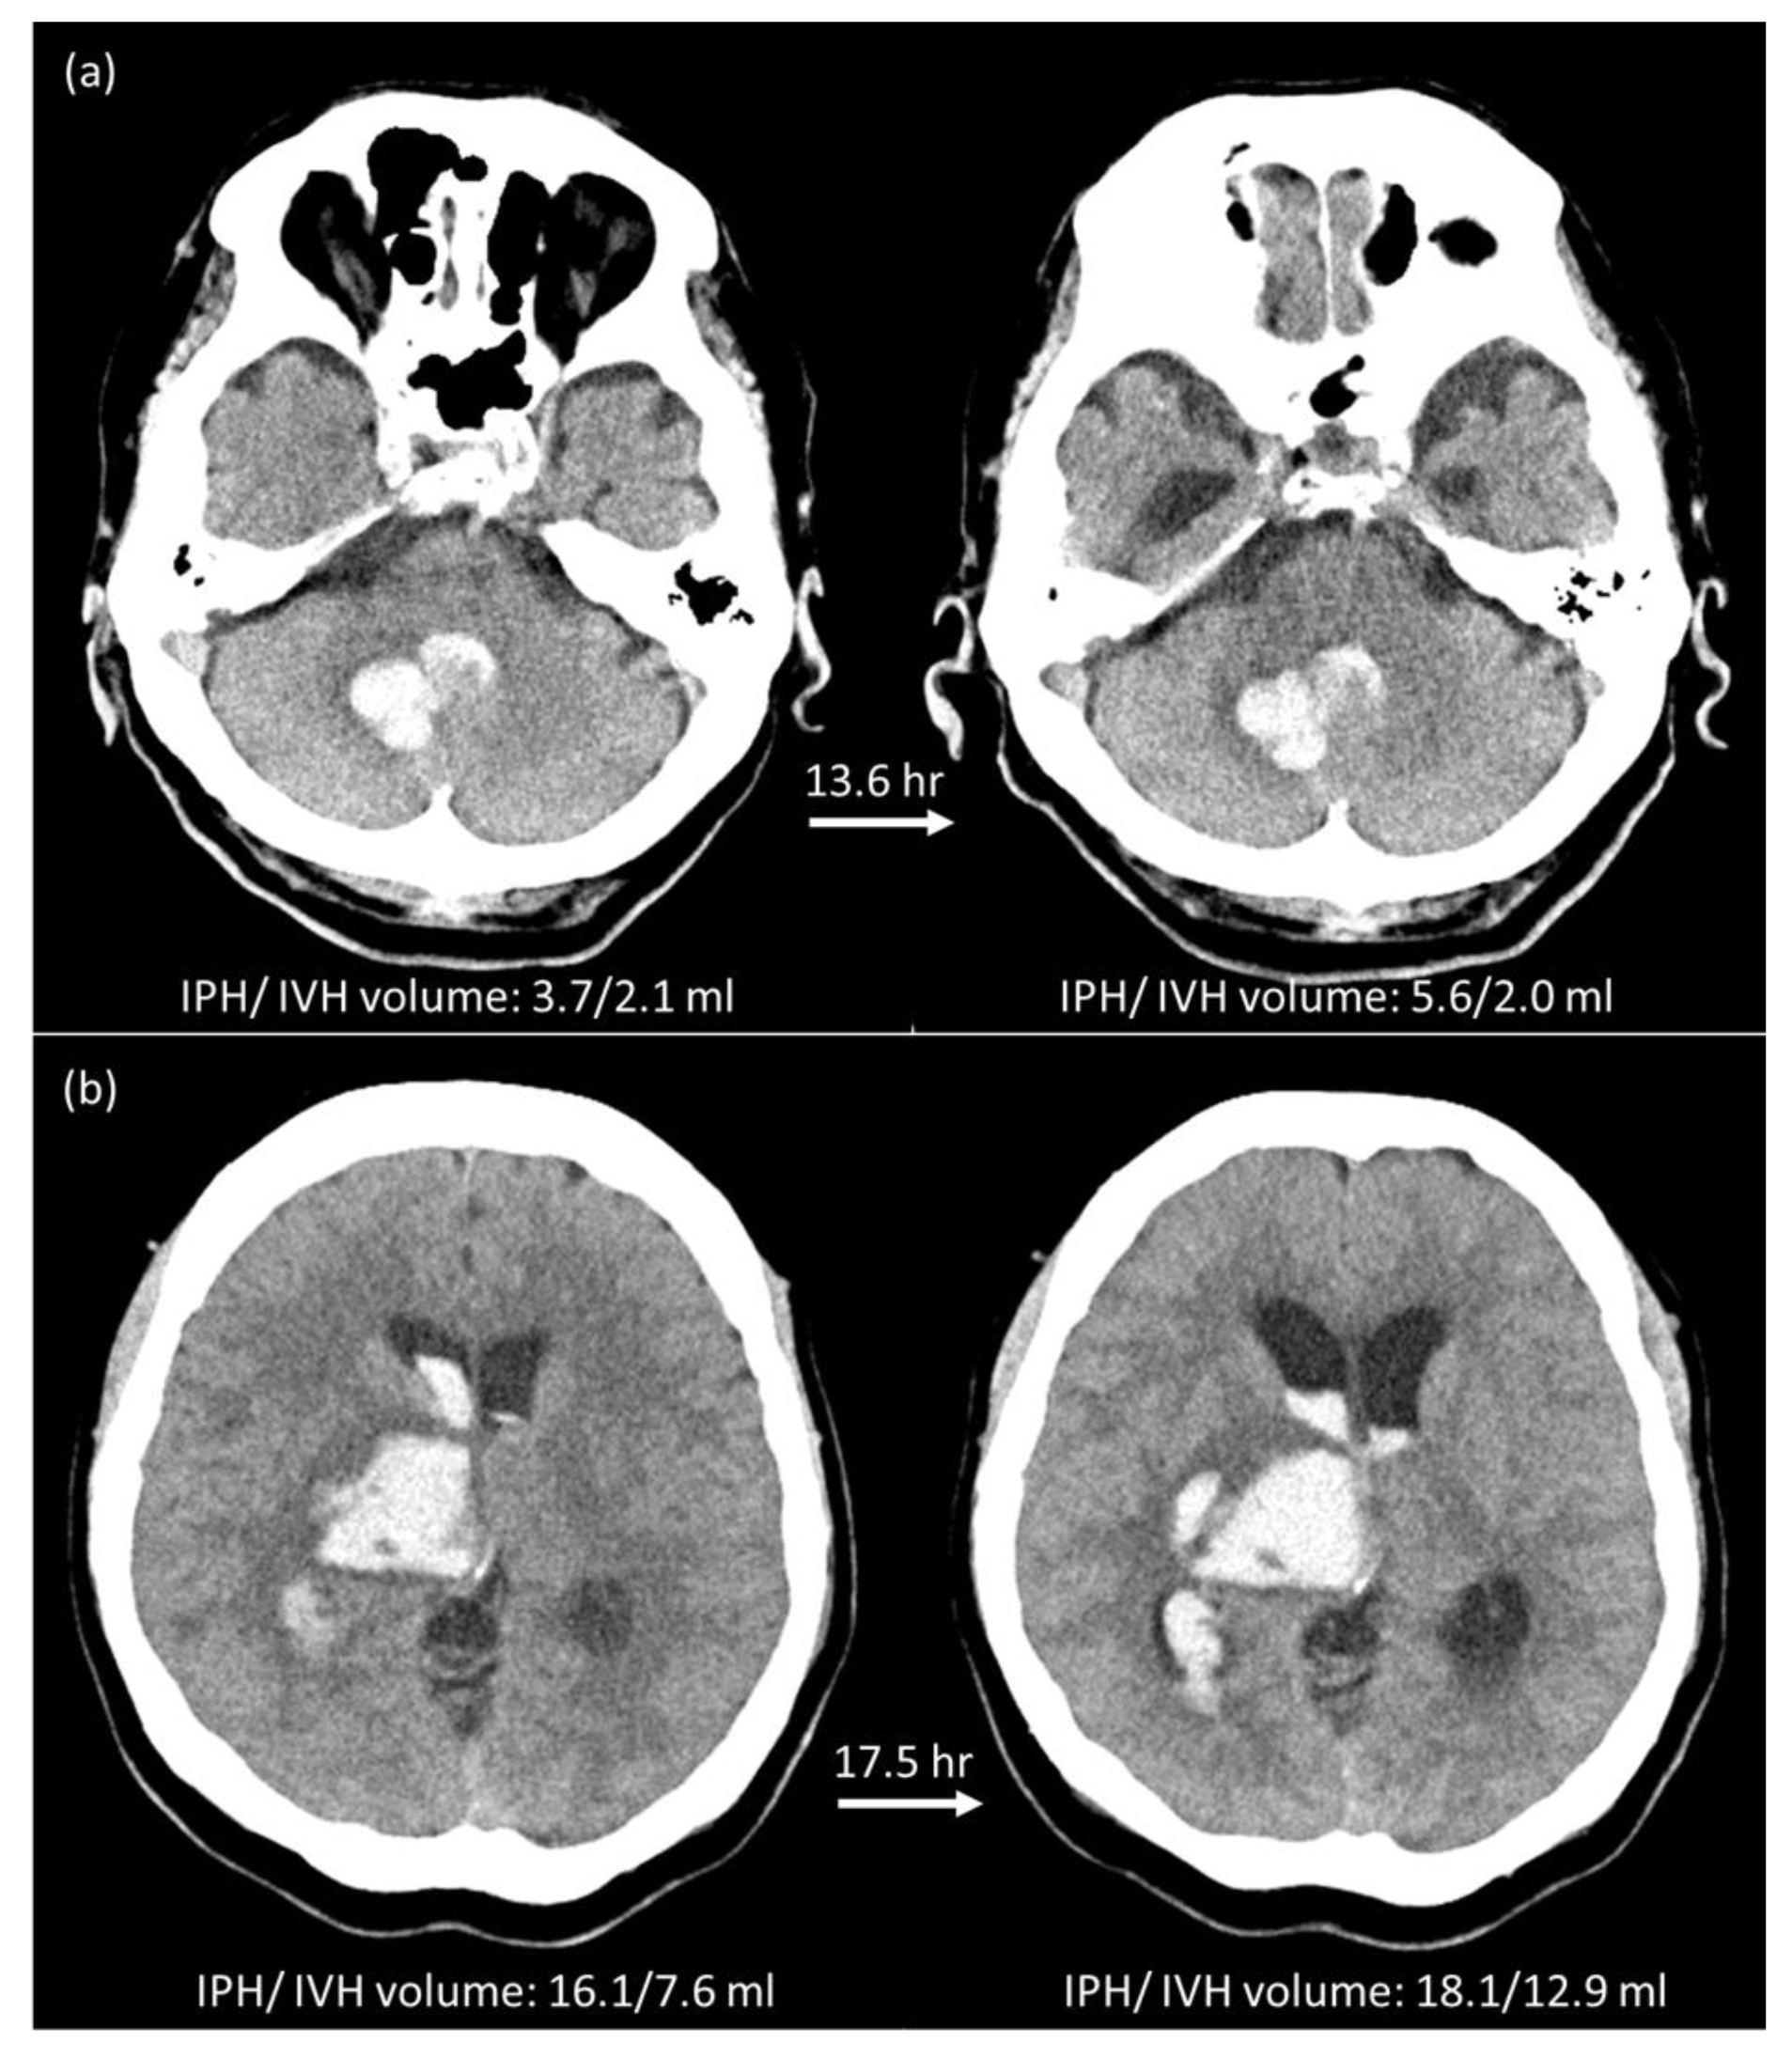

2.5. Manual Hematoma Segmentation and HE Definition